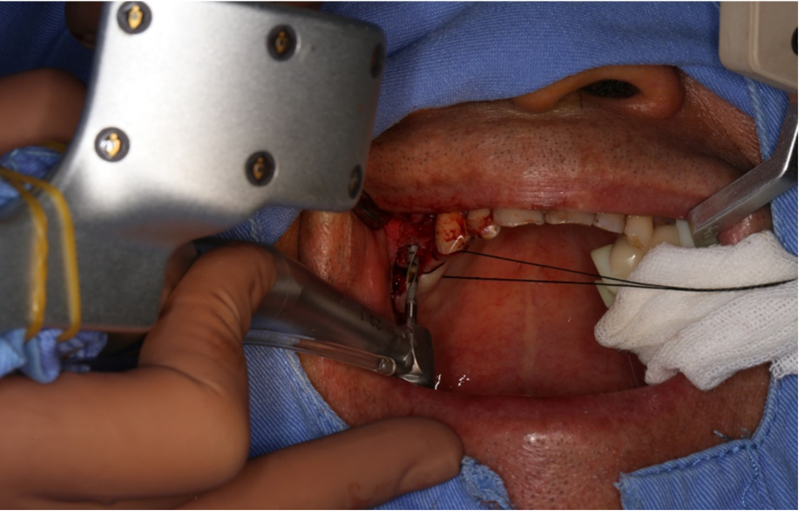

®完成標定及配準

®按照術前方案進行備洞及植體植入

®按照術前方案進行備洞及植體植入,醫(yī)生可以通過屏幕軟件引導對手術中植入點、角度、深度實時追蹤

®對植體深度及方向進行確認

®進行縫合